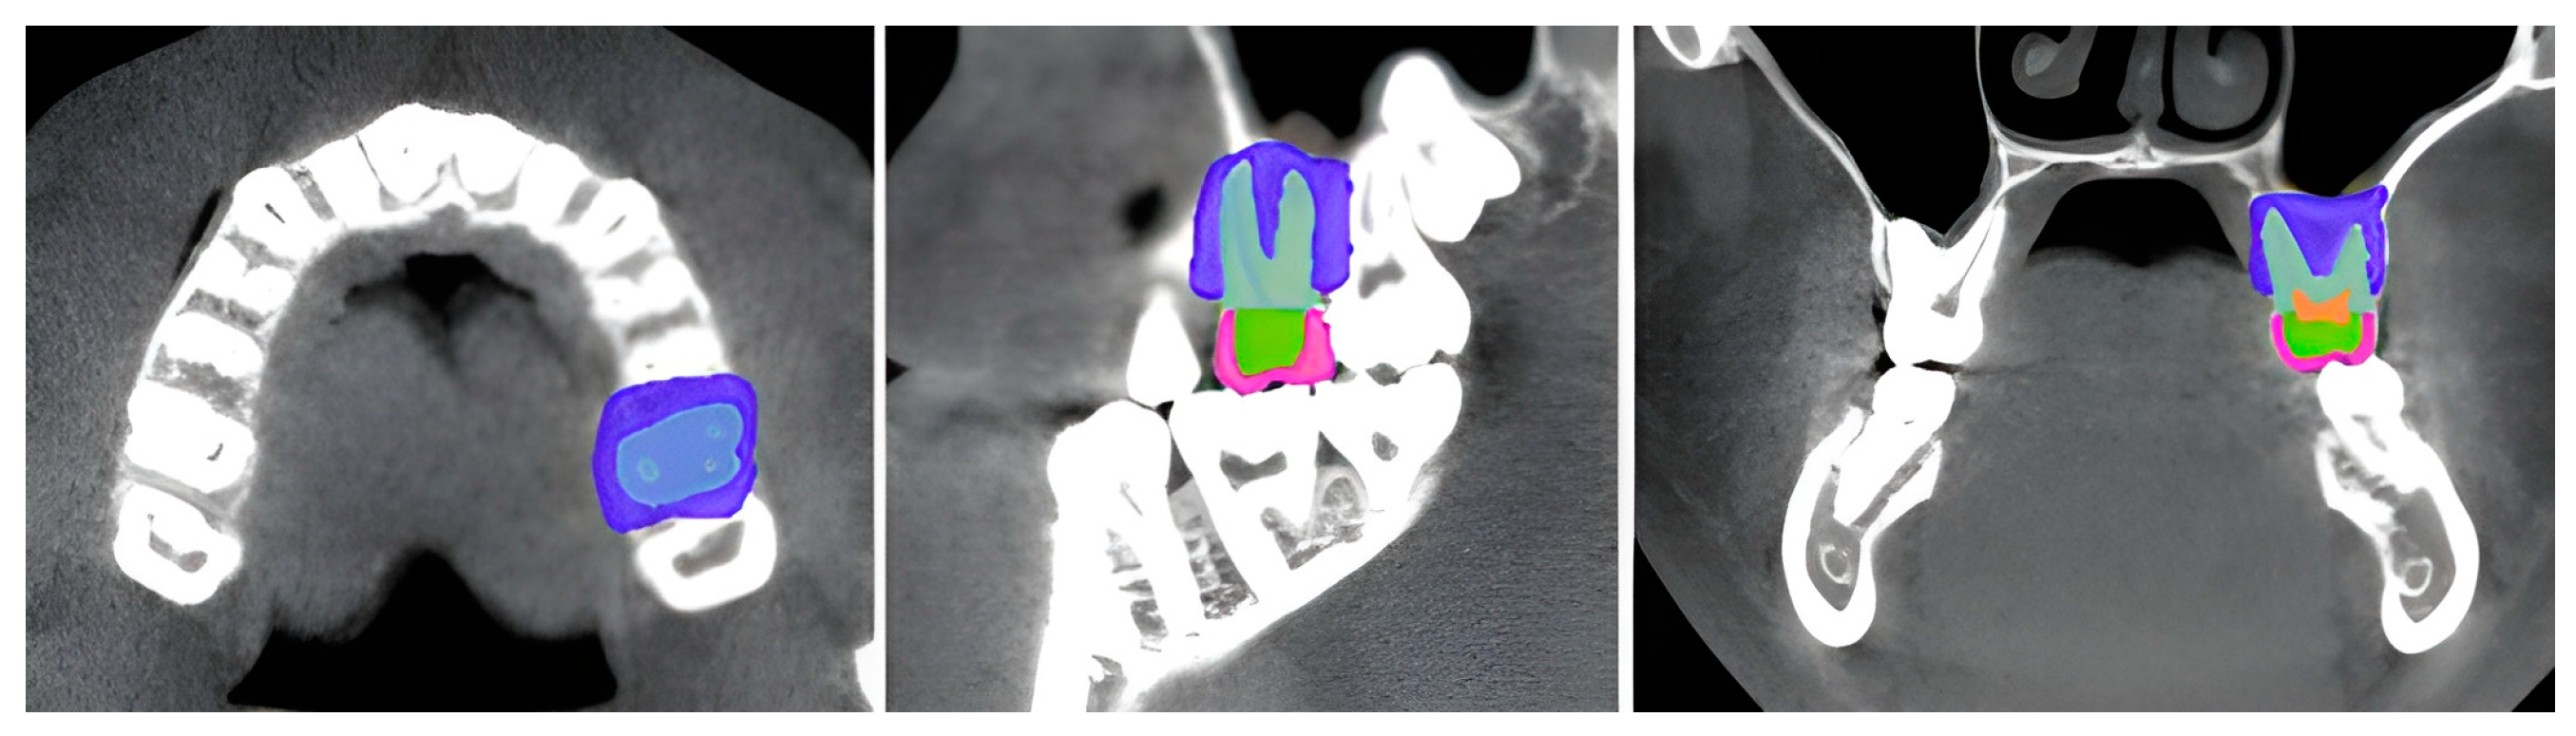

2.2.3. Stress Analysis

3.1. Stress Distribution